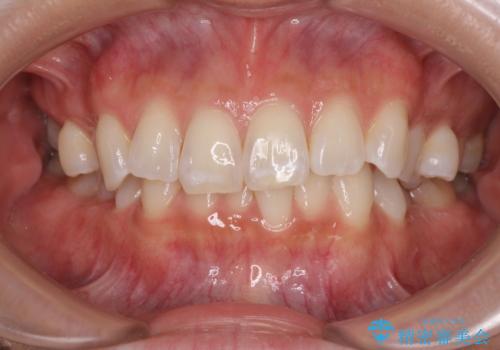

開咬とデコボコを整える インビザライン矯正治療

- 前歯の開咬と叢生を気にして来院された患者様です。

開咬の治療は、前歯を閉じるように動かすとともに、上下臼歯を圧下(骨内にめり込ませる)させることで進めて行きます。

インビザラインは臼歯の圧下を効果的に行えるため、インビザラインを用いて矯正治療を行うこととしました。また、アンカースクリューを用いて、口元の突出感の改善を図りました。